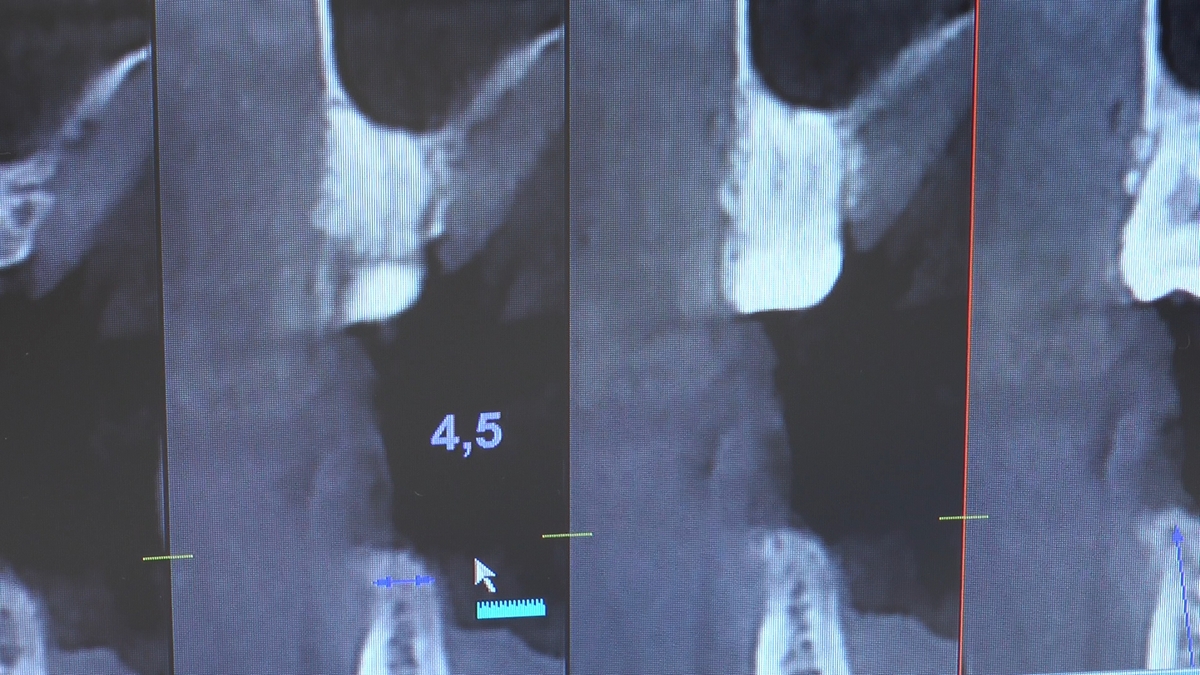

W trakcje dwóch dni zabiegowych, piątek i sobota, 5 i 6 października 2018 roku, lekarze uczestniczący w 6 Sesji VI Sezonu, wykonali wiele zabiegów o wysokim stopniu trudności. Przeprowadzili je pod kierunkiem Mentorów Instytutu Vivadental – dr n.med. Violetty Szycik, dr n.med. Magdaleny Kisłowskiej-Syryczyńskiej oraz dr Małgorzaty Piotrowskiej.

Wprowadziliśmy łącznie 25 implantów w tym wykonaliśmy:

zabiegi regeneracji kości z zastosowaniem materiałów kościozastępczych i kości własnej oraz fibryny bogatopłytkowej,